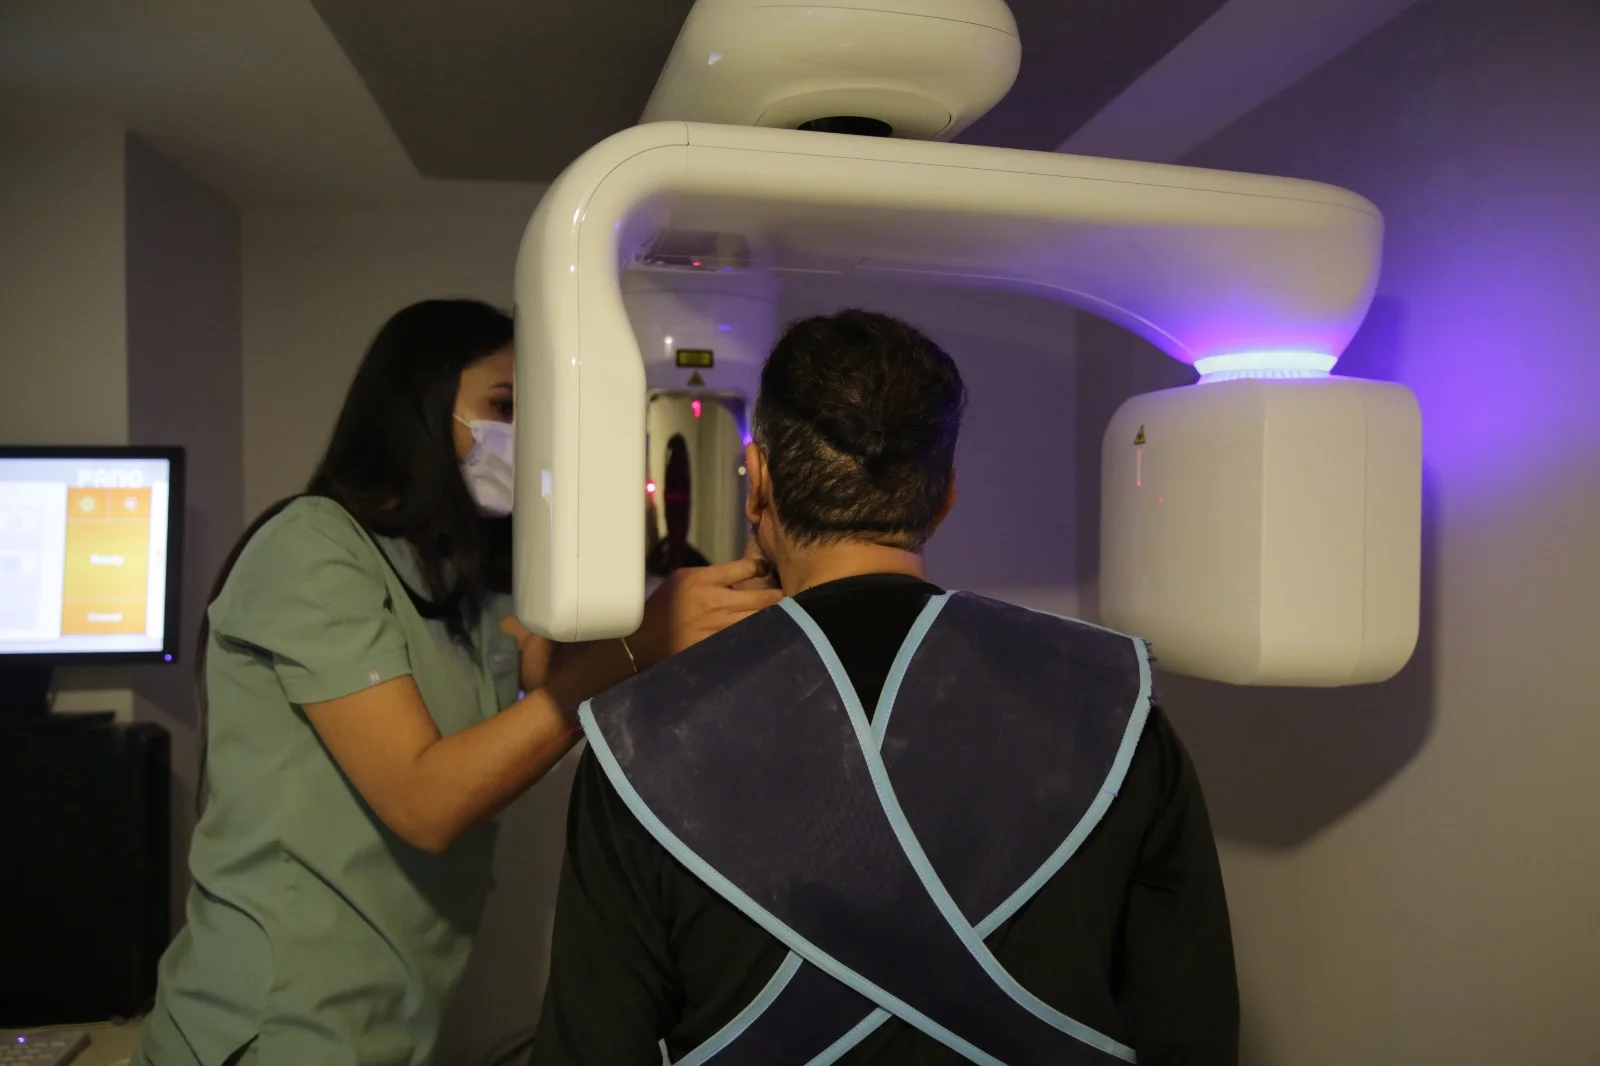

Premium Dental Ekipmanlarla Çalışıyoruz

Planmeca

Yüksek teknoloji dijital görüntüleme sistemleri

Klinik Galerimiz

Klinik ortamımızı ve tedavi süreçlerimizi yakından inceleyin